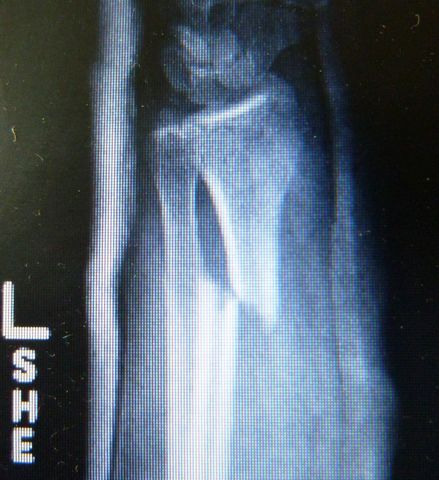

| Back in Tampa, I ordered films of Alison's arm for presentation to her orthopedic surgeon. | |

| Alignment is not perfect, but I was told that closed reductions involve a bit of luck, and no ground has been lost because healing does not commence for a few weeks. After a curbside conference, he indicated that the best plan for optimal alignment and minimal cast time would be a plate and screws, usually not palpable or visible from the outside after healing. | |

He fitted the margins perfectly back into place, laid a

plate into position, drilled a few holes, and screwed the plate

onto the bone.![]() |

Dr. Gray used flouroscopy to confirm that the fracture margins were in perfect alignment, secured by three screws proximal and three screws distal to the fracture. |

|

| In fact, one view (below right) shows such tight apposition and such perfect alignment, that one cannot even see the fracture margins. | |

Dr. Gray checked all of her wrist bones (left), applied a new plaster splint and a new sling, and Alison's I.V. line was removed about 2.5 hours after it was inserted. What a great surgeon and professional team! |